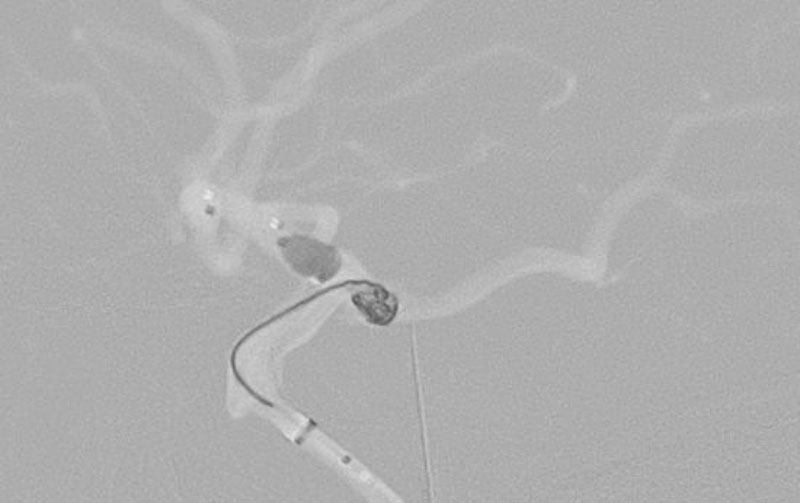

No.1630 手術前

No.1630 手術中

No.1630 手術後